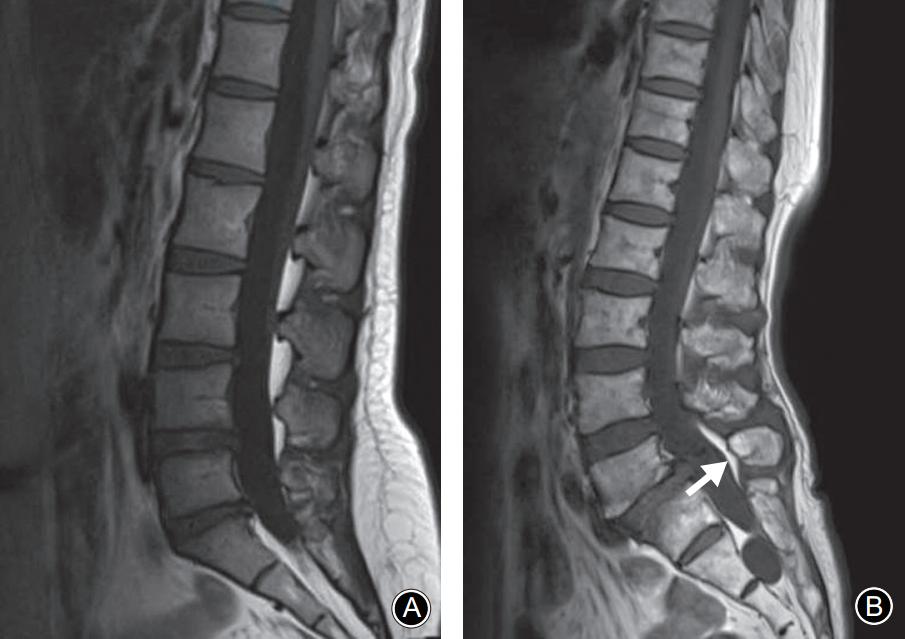

在峡部裂继发的椎体滑脱患者中MRI正中矢状面TIWI示棘突基底部与硬膜之间会出现脂肪的异常增多沉积,且椎体滑脱越严重脂肪增多也越明显。 而在尚未出现椎体滑脱的隐匿性峡部裂患者中是否也存在上述脂肪增多的影像学表现呢?最近,一项回顾性研究发现棘突基底部与硬膜之间的脂肪沉积征对隐匿性腰椎峡部裂的诊断有一定的特异性,有助于早期诊断峡部裂。

腰椎MRI正中矢状面 T1WI。A:棘突基底部和硬膜之间未见脂肪沉积;B:L5棘突基底部与硬膜之间可见线状脂肪高信号带(箭头示)

L5椎弓峡部裂典型病例一:男,32岁。A,B: 腰椎正位侧位X线片示无明显椎弓峡部裂征象; C: 腰椎 MRI正中矢状面T1WI示L5棘突基底部与硬膜之间出现脂肪高信号带(箭头示); D: 腰椎CT矢状面重建示L5椎弓峡部骨质不连(箭头示)。

L5椎弓峡部裂典型病例二:男,35岁。A,B: 腰椎正位侧位X线片均无明显椎弓峡部裂征象; C: 腰椎MRI正中矢状面T1WI示L5棘突基底部与硬膜之间出现脂肪高信号带(箭头示); D: 腰椎CT矢状面重建示L5椎弓峡部骨质不连,裂隙较细(箭头示)。